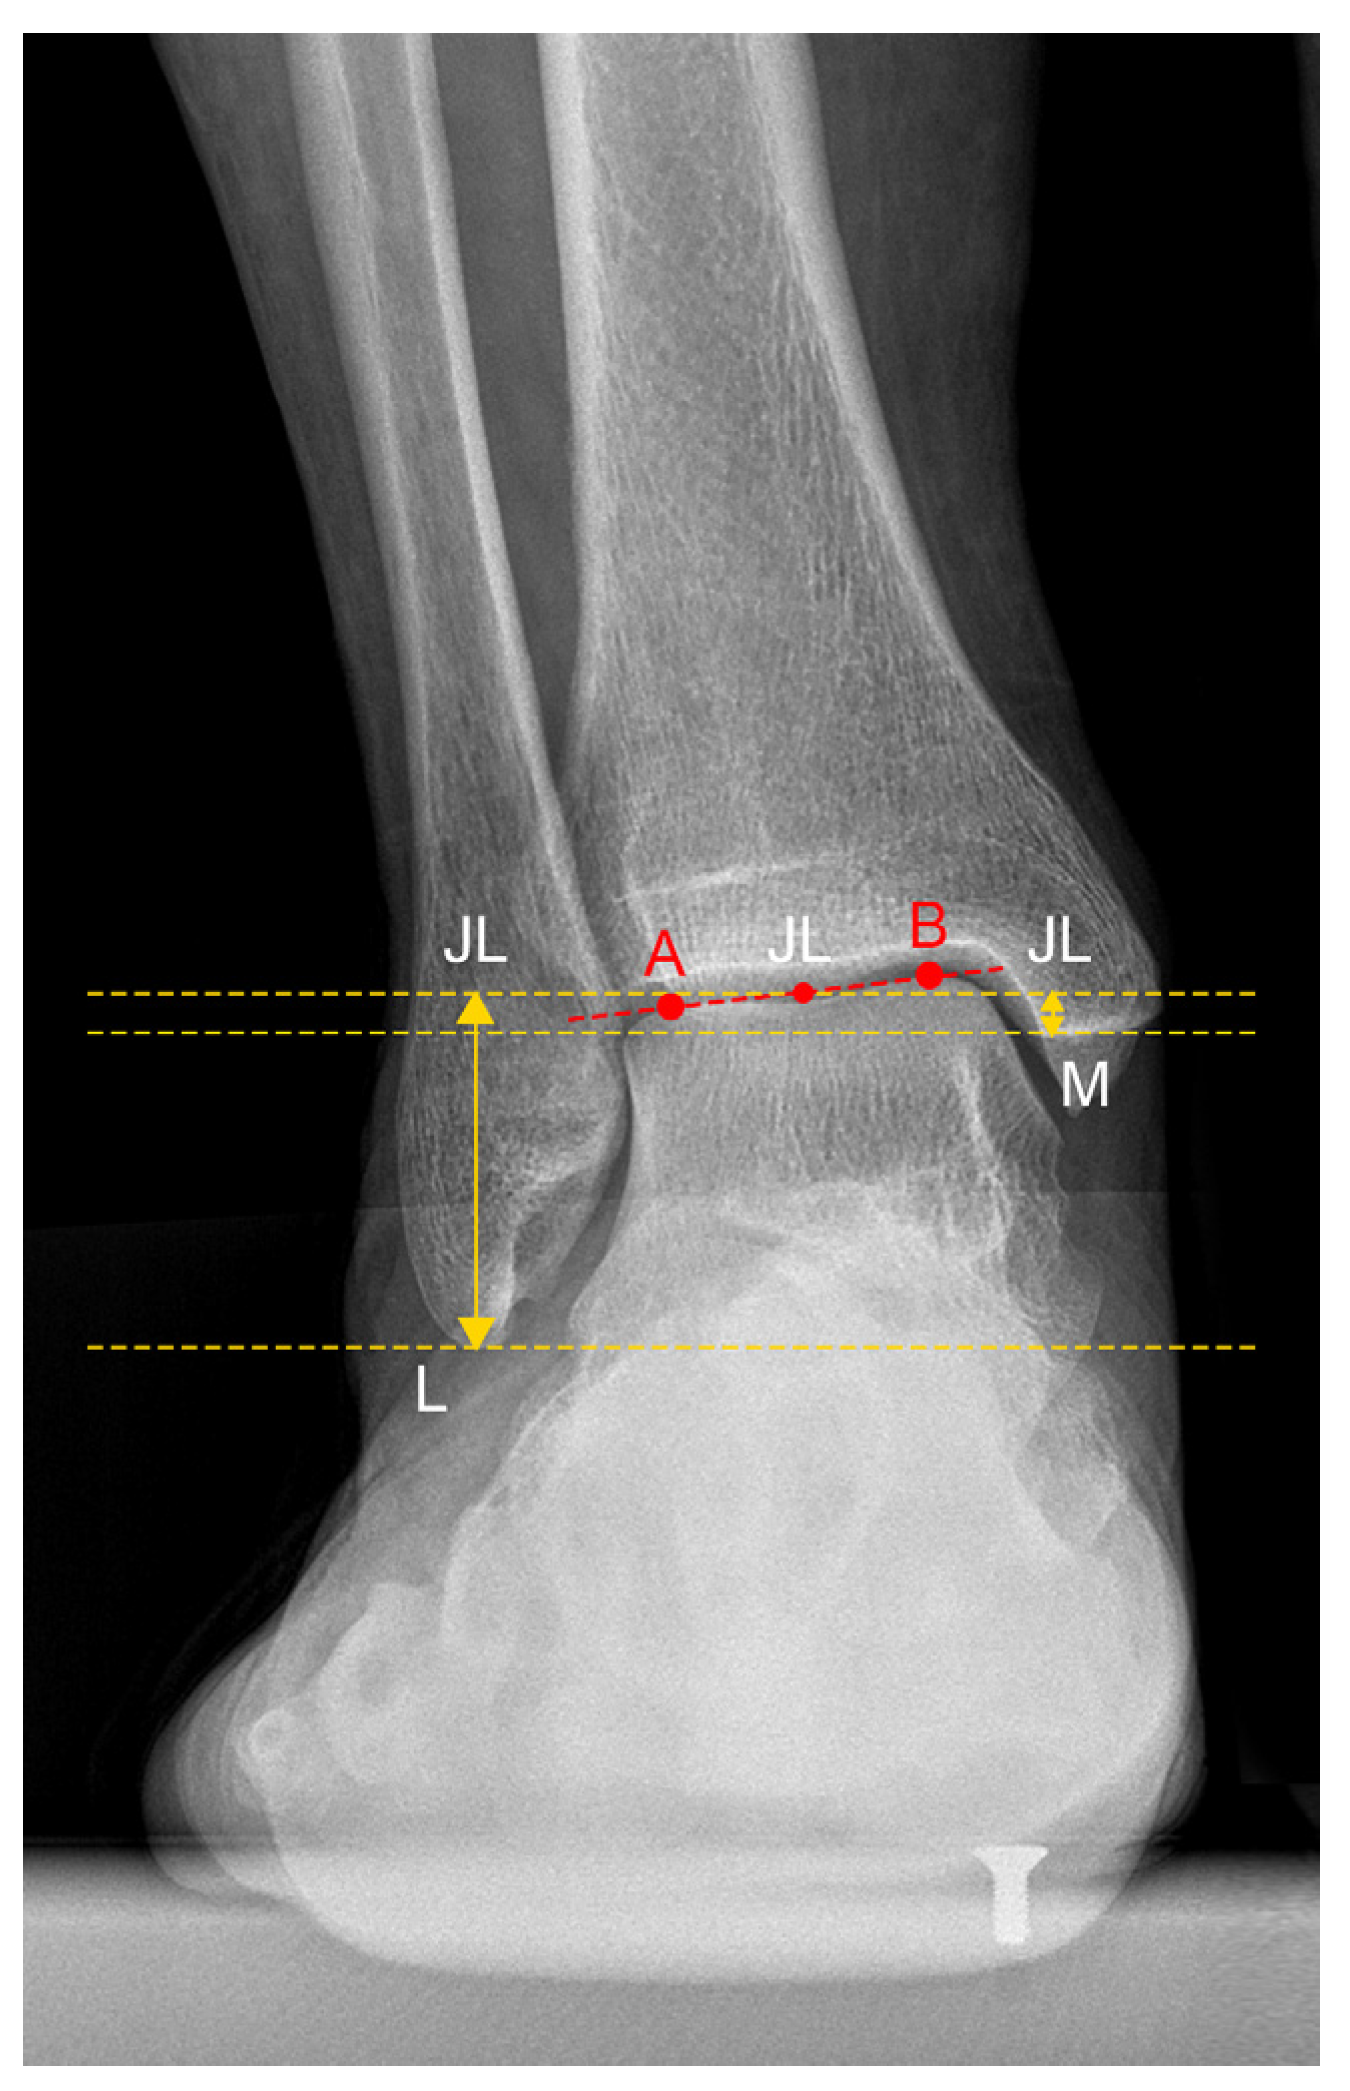

| JLHR 1 | 2.23 ± 0.54 | 1.94 | 1.64–3.44 | 24.3% |

| LM-JL 2 distance | 2.30 ± 0.39 cm | 2.12 cm | 1.78–3.19 cm | 17.0% |

| MM-JL 3 distance | 1.21 ± 0.30 cm | 1.11 cm | 0.89–1.78 cm | 24.9% |

| CS-JL 4 distance | 3.82 ± 0.51 cm | 3.87 cm | 2.94–4.53 cm | 13.4% |

| JLHR 1 (contralateral) | 1.95 ± 0.54 | 1.92 | 1.49–3.54 | 27.7% |

| LM-JL 2 distance (contralateral) | 2.21 ± 0.26 cm | 2.12 cm | 1.84–2.81 cm | 11.8% |

| MM-JL 3 distance (contralateral) | 1.00 ± 0.20 cm | 0.92 cm | 0.76–1.42 cm | 20.3% |

| CS-JL 4 distance (contralateral) | 4.04 ± 0.32 cm | 4.06 cm | 3.46–4.53 cm | 7.8% |